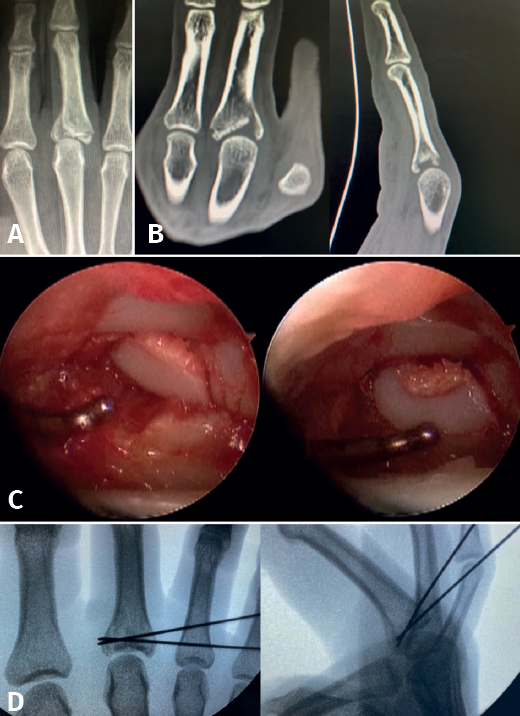

As with Bennett fractures of the thumb, fractures involving the articular surface, both of the common metacarpal head (less commonly) and of the base of the proximal phalanx, can be evaluated and treated with an arthroscopically assisted approach(9).

There are authors who divide the joint fractures into two groups(1):

- Intra-articular fractures proper, caused by compression or shear mechanisms.

Once the fragments have been reduced, 0.8 or 1.0 Kirschner wires are used to maintain reduction (Figure 7). Sometimes we can only maintain reduction by applying a stop, to prevent the osteochondral fragment from collapsing. Depending on the fracture pattern and the surgeon's preference, we can use conventional screws, cannulated screws, etc. (Figures 8 and 9).